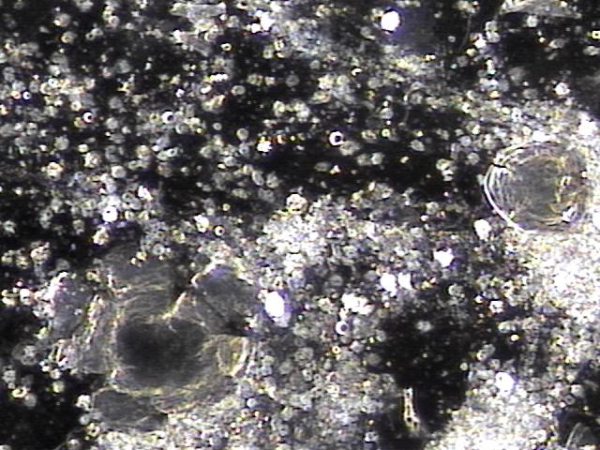

탈락된 상피세포로 좁아진 사정관과 전립선관 그리고 사정관 입구의 결석들이 배출시 손상된 조직 치료되고 전립선의 표적치료후 치료된 전립선과 사정관 결석과 염증세포 덩어리의 현미경학적 자료입니다.

This is a microscopic image showing treated prostatic and ejaculatory duct stones, along with clusters of inflammatory cells, after targeted therapy of the prostate. It illustrates the healing of tissues damaged during the expulsion of dislodged epithelial cells, which had narrowed the ejaculatory ducts, prostatic ducts, and ejaculatory duct openings.